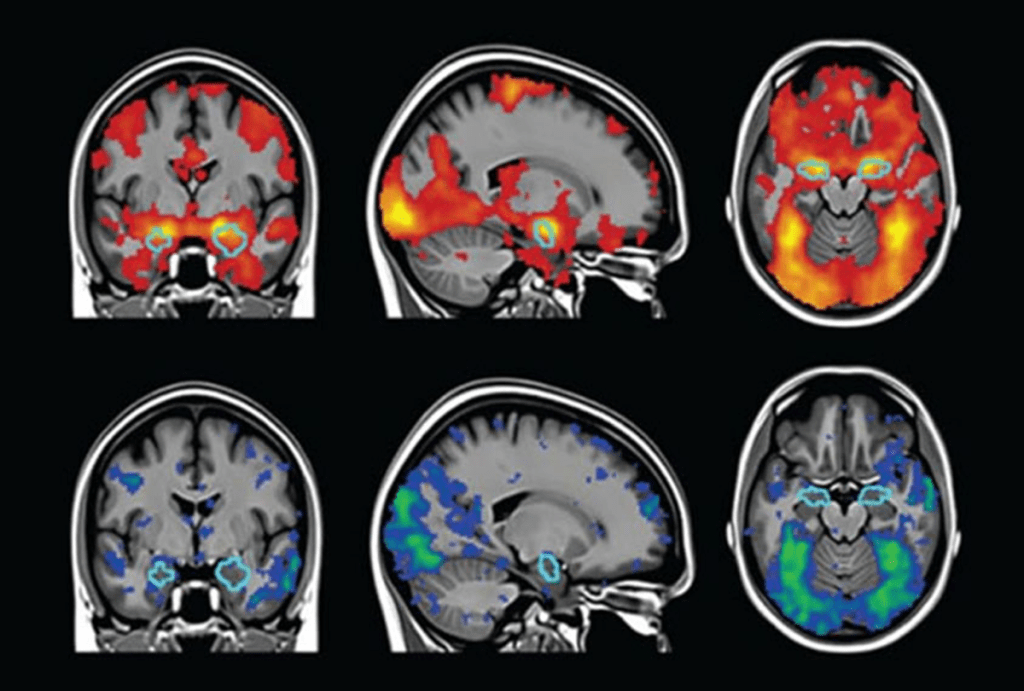

I find this tremendously hard to believe that AI will be able to read our minds. fMRI scans measure blood flow or blood-oxygen-level dependent (BOLD) readings. They look like this:

I just don’t believe there’s enough information in such images to generate an image of what’s in a person’s mind’s eye. However, I thought about how it might be possible to get the results described in this experiment.